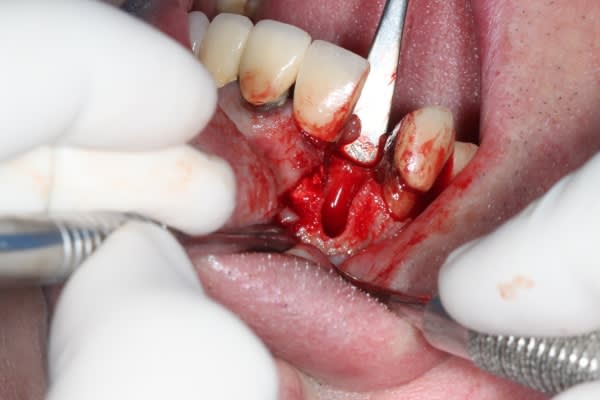

juste pour le plaisir

un petit dernier mis en fonction la semaine dernière

1 pbr75u - Eugenol

2 wlbqqs - Eugenol

3 soqqmc - Eugenol

4 peblmt - Eugenol

5 ebbipt - Eugenol

Img 8465 fqhxid - Eugenol

Juste une remarque sur tes photos Michael, puisque sur la chirugie tu maitrises parfaitement : irrigues ton site avant de prendre une photo et enlèves les taches de sang sur les dents adjacentes, ça ne change en rien la qualité de ton travail, mais c'est plus propre et plus agréable à regarder.